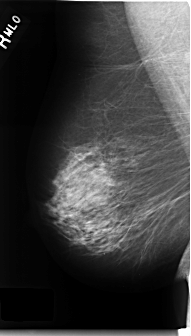

C_0228_1.RIGHT_MLO

C_0228_1.RIGHT_CC

RIGHT_CC LINES 4712 PIXELS_PER_LINE 2648 BITS_PER_PIXEL 12 RESOLUTION 50 NON_OVERLAY

RIGHT_MLO LINES 4704 PIXELS_PER_LINE 2672 BITS_PER_PIXEL 12 RESOLUTION 50 NON_OVERLAY